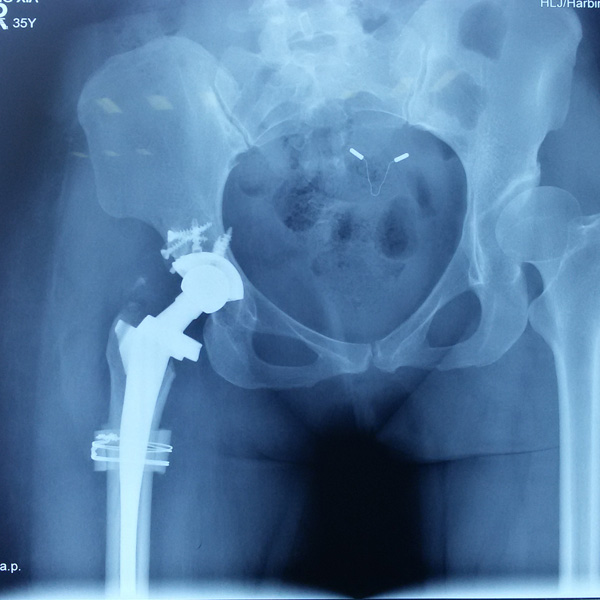

手術(shù)后手術(shù)前

骨肉瘤手術(shù)

患者張某,女,14歲,診斷為“左股骨遠(yuǎn)端骨肉瘤”,當(dāng)?shù)蒯t(yī)院因?yàn)獒t(yī)療技術(shù)和能力的限制,只能考慮截肢手術(shù)。患者家屬通過平臺(tái)推薦,指定到哈......